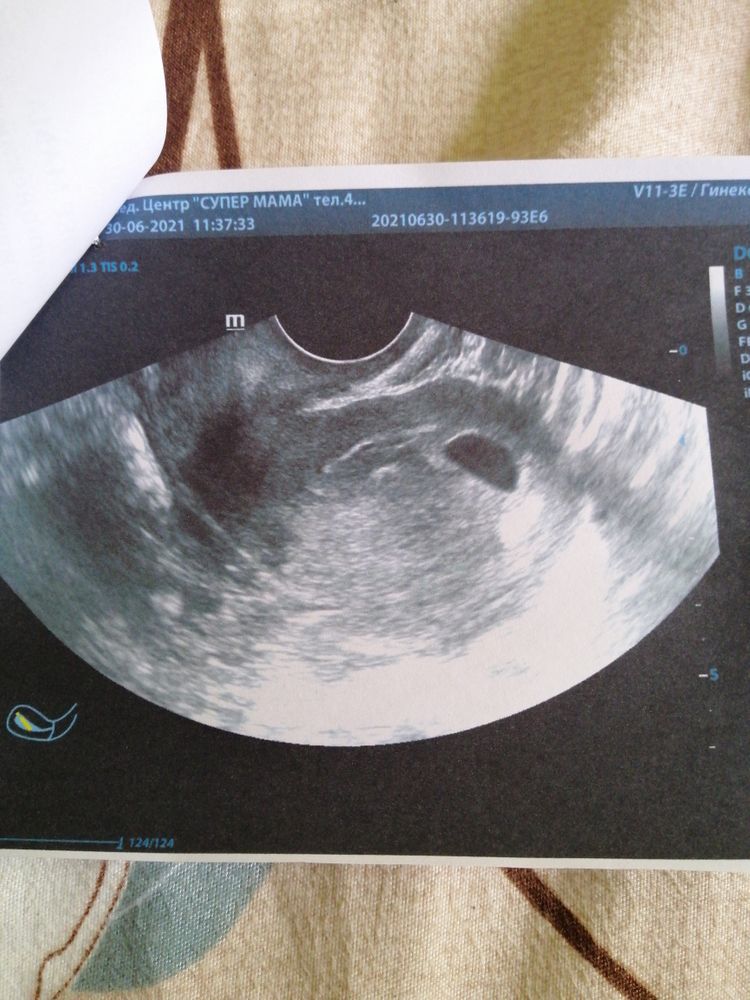

Я вам уже, вроде, писала свою историю. У вас размер ПЯ в среднем всего 12 мм, это абсолютно нормально, что там ничего не видно. У меня при ПЯ 21 мм не нашли ничего, даже ЖМ, который 100% при таком размере должен быть, и поставили анэмбрионию, а через 6 дней я пришла и все уже было на месте, хотя честно говоря, я с врачем уже обсудила, где сделать чистку из за анэмбрионии. Не стоит переживать из за того, на что вы не можете повлиять. Все разрешится так, как надо. Желаю вам удачи 🤞

А какой срок и размер плодного яйца? Размер не маленький, вроде, эмбрион уже должен быть виден…

Изображение Диана,